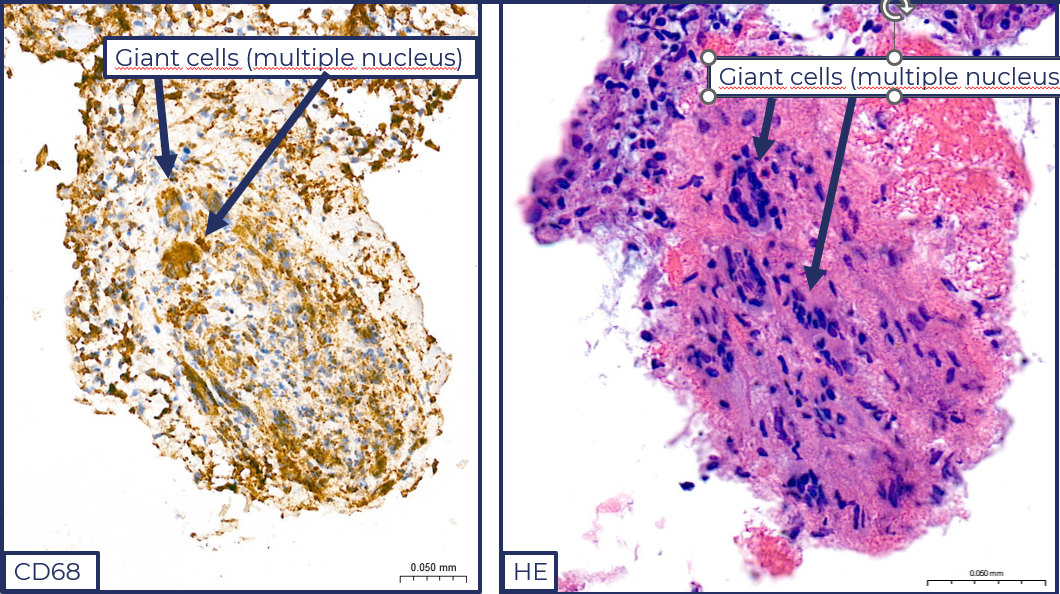

Our 52-year-old female patient has no significant medical history; she had an upper respiratory tract infection prior to admission. She presented to the ER with chest pain and dyspnea. ECG showed anterior ST-elevation. Urgent coronary angiography showed an intact coronary system. Initially, she was hemodynamically stable, and echocardiography showed a mildly reduced EF. During a short observation period, her condition rapidly progressed, she became hypotonic, and due to third-degree AV block and significant pausa, temporary PM implantation was performed. She was admitted to our clinic due to suspected progressive myocarditis. Her condition stabilized with dual circulatory support. Due to continuous PM requirement, performing cardiac MRI was not possible. Cardiac biopsy confirmed giant cell myocarditis. We started high-dose IV steroid therapy. As a result, left ventricular function improved and necroenzyme levels decreased. According to the latest literature recommendations, her steroid treatment was supplemented with mycophenolate mofetil and tacrolimus, which gradually improved the EF and AV conduction, eliminated the need for a pacemaker, we removed the iPM, and stopped the inotropes and vasopressors. Extensive bacteriological, viral serological and immunological tests did not confirm active infection or immunological abnormalities. Cardiac MRI showed good left and right ventricular ejection fractions and late non-ischemic contrast enhancement. She was discharged after 2 weeks of treatment in a stable clinical condition, with the use of complex immunosuppressive therapy. She receives regular follow-up in the heart transplantation department of our clinic. With immunosuppressive treatment, she is symptom-free, EF 60%, and has no arrhythmia or conduction disorders.

Our patient's case draws attention to the fact that in case of suspected myocarditis, myocardial biopsy and rapid diagnosis can be life-saving. It is rare that with combined immunosuppressive therapy and regular follow-up over a period of 1 year, the patient remained symptom-free, had good cardiac function, and was able to avoid possible heart transplantation and implantation of a circulatory support device.